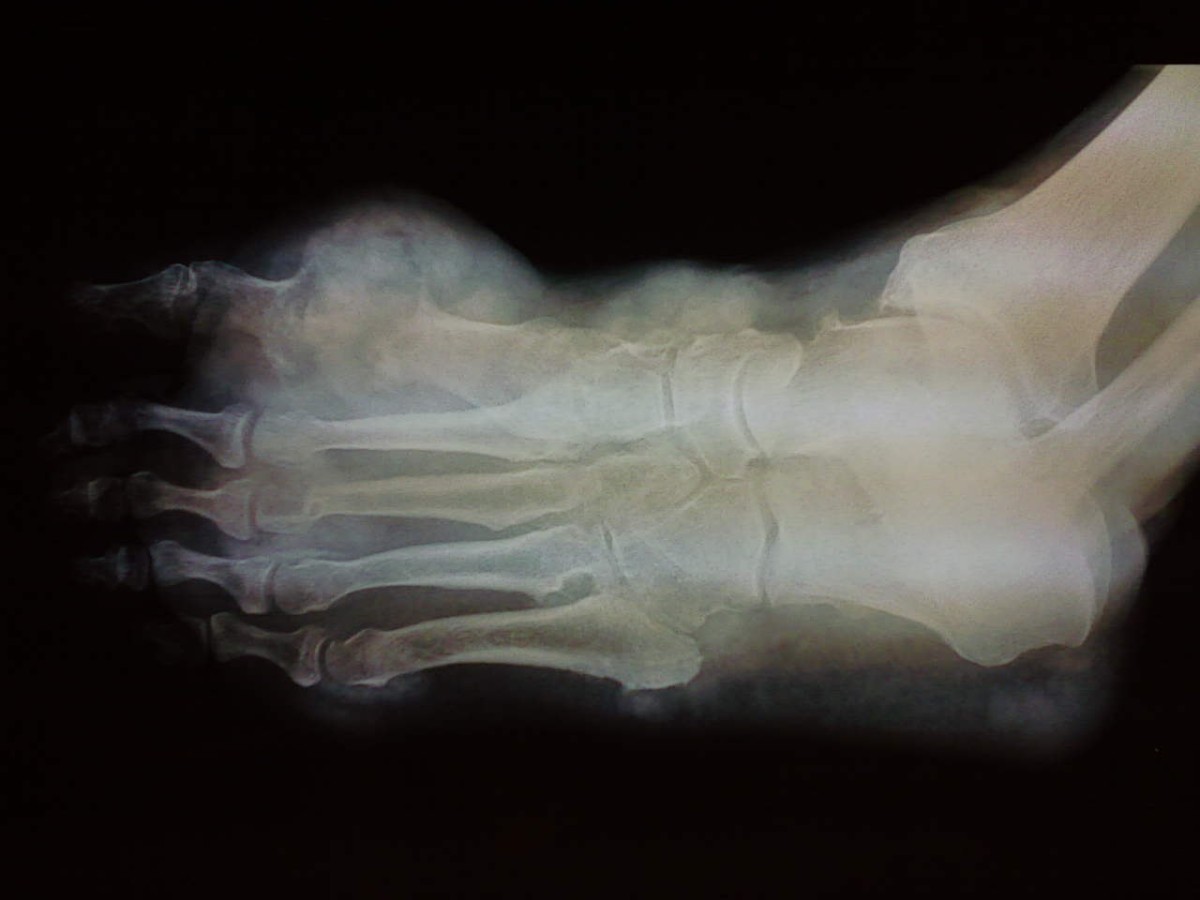

Gout Foot Ulcers . Gout is the most common type of inflammatory arthritis. Tests to help diagnose gout. A gout diet may help decrease uric acid levels in the blood. Ulcers can get infected and sometimes require amputation of your foot or toes. Gout is a general term for a variety of conditions caused by a buildup of uric acid. Gout happens when there’s a buildup of uric acid in your body. A gout diet isn't a cure. It causes sudden and intense attacks of joint pain, often in the big toe and at night. But it may lower the risk of recurring gout. Doctors usually diagnose gout based on your symptoms and the appearance of the affected joint. Gout most commonly affects your big toe joint. It’s important to identify and treat it early to avoid pain and complications. Gout can be extremely painful and incapacitating but is extremely treatable in almost all patients. Healing the ulcer might include nonsurgical and surgical. If you have gout, you’ll probably feel swelling and pain.